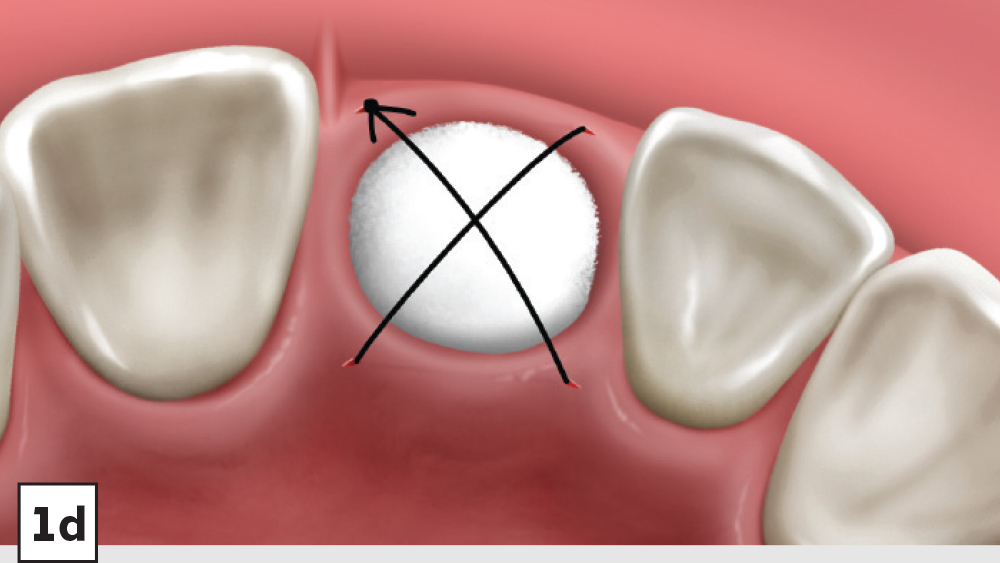

1. Membrane: A Newport Biologics Resorbable Collagen Plug should be cut in half and hydrated with 0.9% sodium chloride. The plug is compressed and placed over the socket, extending the collagen underneath the reflected subperiosteal pouch to increase retention.

2. Closure: Closure should be completed with a high-tensile suture material, such as polyglycolic acid (PGA) or PTFE, with a crisscross suture technique (Table 2). Care should be exercised to avoid suturing through the membrane. Gut sutures (plain, chromic) should be avoided, as they have a compromised tensile strength and will increase the probability of bone graft and membrane loss.